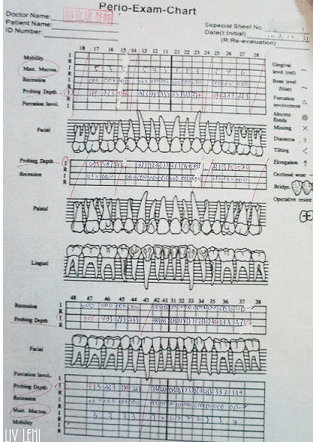

由於我是 輕微的牙齦炎,X光片 出來的結果也良好,

所以進行了必要的 牙周囊袋測量 後,

醫師判斷,我只需要 第一階段治療➔ ➔

所有治療前都必須透過 牙周囊袋測量,

來判別牙周受破壞的程度、以及需要何種治療,

醫師會先拿一根 牙周探測器,插入牙齦溝測量深度,

健康時,牙齦溝的深度大約1~3釐米,

大於3釐米就表示已形成囊袋,越深代表牙周破壞越嚴重。

我的全口牙周囊袋測量數值,前面牙齒都是3釐米,

越後面的牙齒有4、5釐米的深度,

有2顆更誇張,直逼7和8釐米(右下與左下最後一顆)

越後方的牙齒越難清潔,

因此通常我的囊袋在最後幾顆牙齒都較深><

這個步驟是醫師拿牙周探測器,

測量經過刮除治療與正確刷牙後,牙周囊袋有無改善。

前排牙齒變得更健康了,從原本的3釐米,變成2釐米,

後面囊袋4、5、7、8釐米的深度,都恢復成3釐米了!!